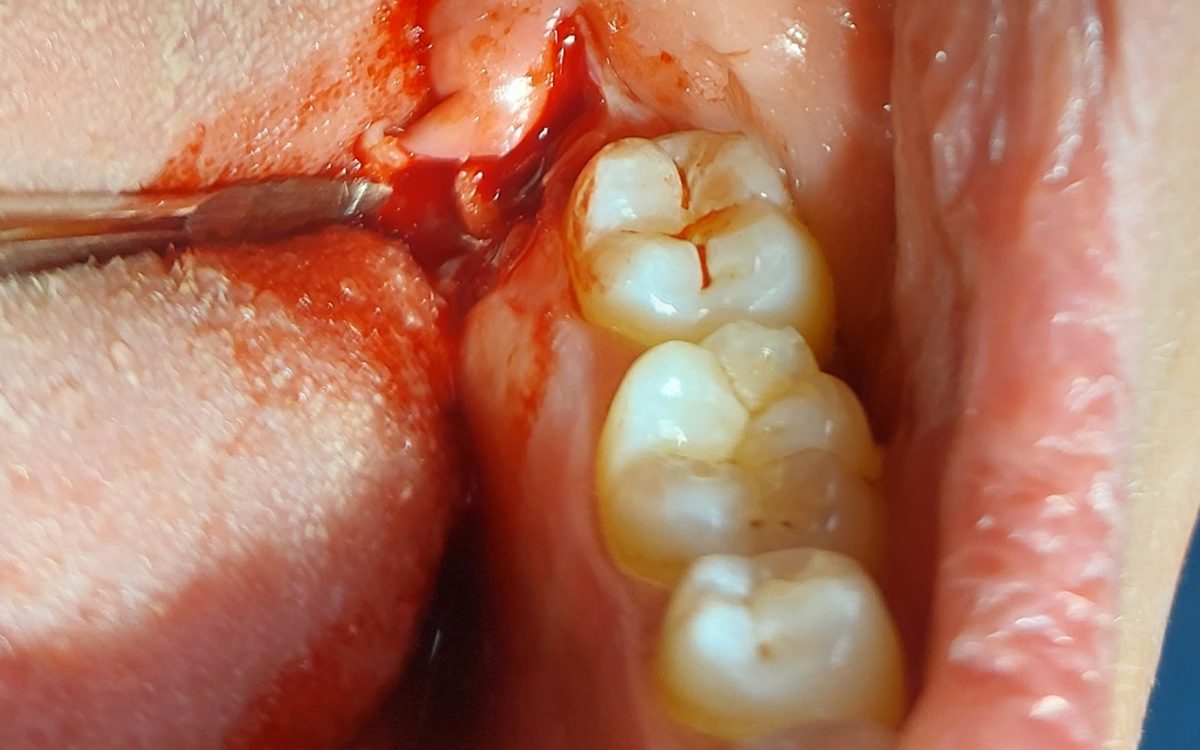

Bölcsességfog eltávolítása

Bölcsességfoga manapság már nem mindenkinek van, de sajnos még gyakorta előfordulnak. Sokszor későn, általában felnőttkorban bújnak elő, esetleg elő sem bújnak. Amennyiben panaszt okoznak, eltávolításukra sor kerül teljesen egészséges fogazatú embereknél is.

A bölcsességfognak nem kell szuvasnak, tömöttnek vagy töröttnek lennie ahhoz, hogy komoly fájdalmat vagy problémát okozzon. A legtöbb esetben maguk a fogak teljesen egészségesek, azonban az állcsontban nincsen elegendő hely számukra, ferdén fejlődnek, így torlódást, szuvasodást idézhetnek elő a szomszédos fogakon, vagy feszítést, gyulladást, csont felszívódást váltanak ki a környező szövetekben. A fentiek miatt legtöbbször a környező szövetek, fogak megóvása érdekében van szükség arra, hogy eltávolítsuk őket.